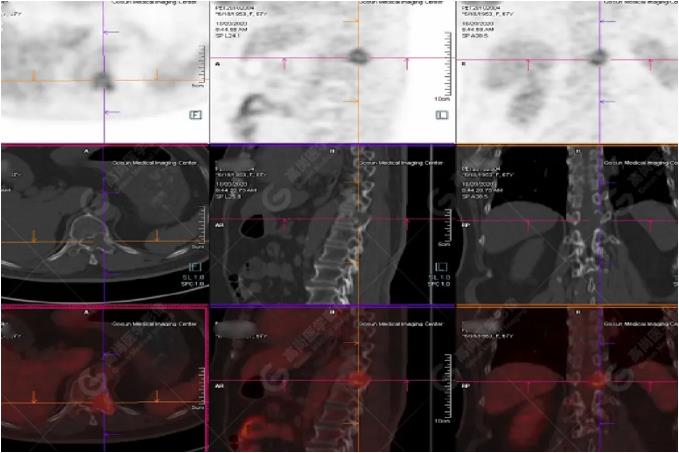

女性 67歲 因背痛查體,糖尿病11年。腫瘤標(biāo)記物:CEA 6.4↑,AFP、CA125、CA199正常。外院MR檢查:胸11椎體-附件左份異常信號,增強環(huán)狀強化,骨原發(fā)?轉(zhuǎn)移?感染?PET/CT影像圖

胸椎溶骨性骨質(zhì)破壞,F(xiàn)DG環(huán)狀代謝增高,SUVmax為4.0。

左側(cè)乳腺一軟組織結(jié)節(jié),F(xiàn)DG代謝增高,SUVmax為2.6。

最終診斷:左側(cè)乳腺癌伴胸椎單發(fā)骨轉(zhuǎn)移。